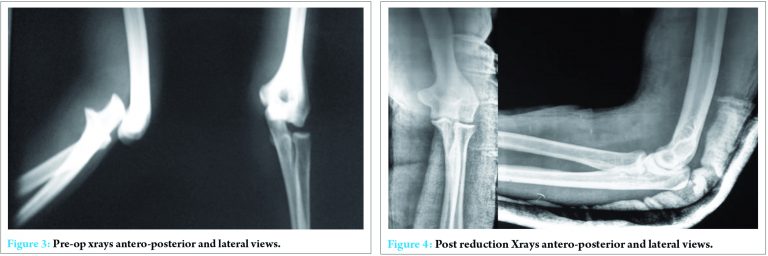

Plain radiography showed anterior dislocation of the elbow (Fig. 3). Preoperatively, brachial and ulnar arterial flow was not recordable with Doppler, but monophasic response was present in radial artery.

Closed reduction was done under intravenous sedation in the minor operating room, and the elbow joint was found to be stable post reduction. The reduction maneuver being traction at wrist and counter traction at the arm, mild flexion and posterior displacement of forearm. The postreduction radiograph (Fig. 4) and computed tomography (Fig. 5) showed congruent reduction. This was done immediately following closed reduction. As there was severe swelling and the distal vascularity insufficient, an attempt of closed reduction was done before the vascular surgeon assessed the limb vascularity, in the idea to reduce the ischemia time and that the compression of the neurovascular structures by the dislocated bony parts, could be temporarily relieved by closed reduction of the elbow joint before contemplating over open reduction or any vascular procedure.